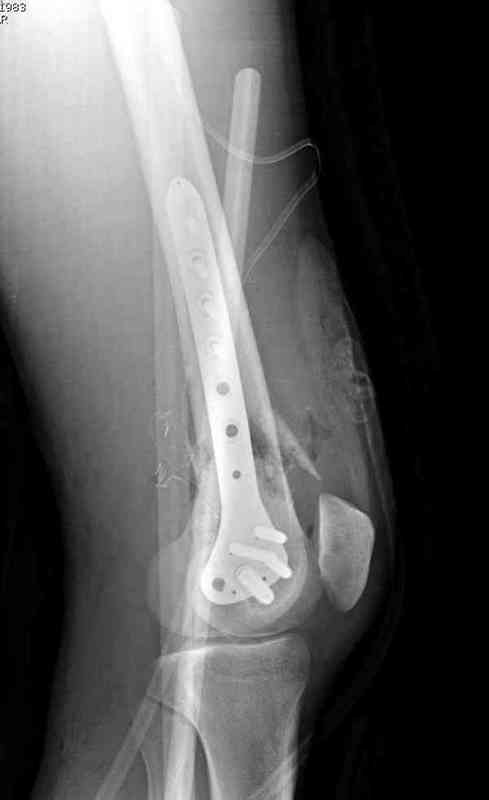

Предпочтительно фиксацию провести пластинами, во-первых, можно было сделать квадрицепс-пластику по Judet для восстановления движения в суставе, а потом коррекцию и фиксацию кондилярной пластиной с угловой стабильностью. Стерильный турникет на конечность поможет уменьшить кровепотерю во время операции.

До выхода Locking Plate, 95 градусная Blade Plate считалась одним из первых locking concept и фаворитов в лечении супракондилярных переломов и осложнений, потому что лезвие внедряясь параллельно к суставу, что создавало хорошую фиксацию. Для усиления фиксации иногда применяли Schuhli nut, чтобы блокировать шуруп в отверстии

(первый прототип locking concept)